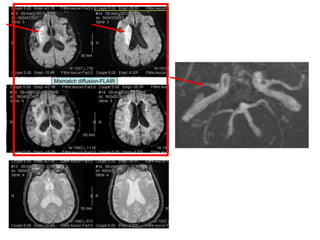

Mismatch diffusion-FLAIR

• Il est 7h30… Attente de

l’hémostase

• 7h45 : INR = 1,47

• Thrombolyse intraveineuse faite aux

urgences

• Evolution clinique:

– Amélioration du déficit neurologique à la fin

de la thrombolyse

– Examen neuro 2 heures plus tard:

• Déficit moteur distal de la main gauche

• Déficit du membre inférieur gauche (chute avant 5

secondes)

• Quadranopsie inférieure gauche

• NIHSS à 2

• Infarctus sylvien gauche étendu

• Présence d’un mismatch Diffusion/FLAIR